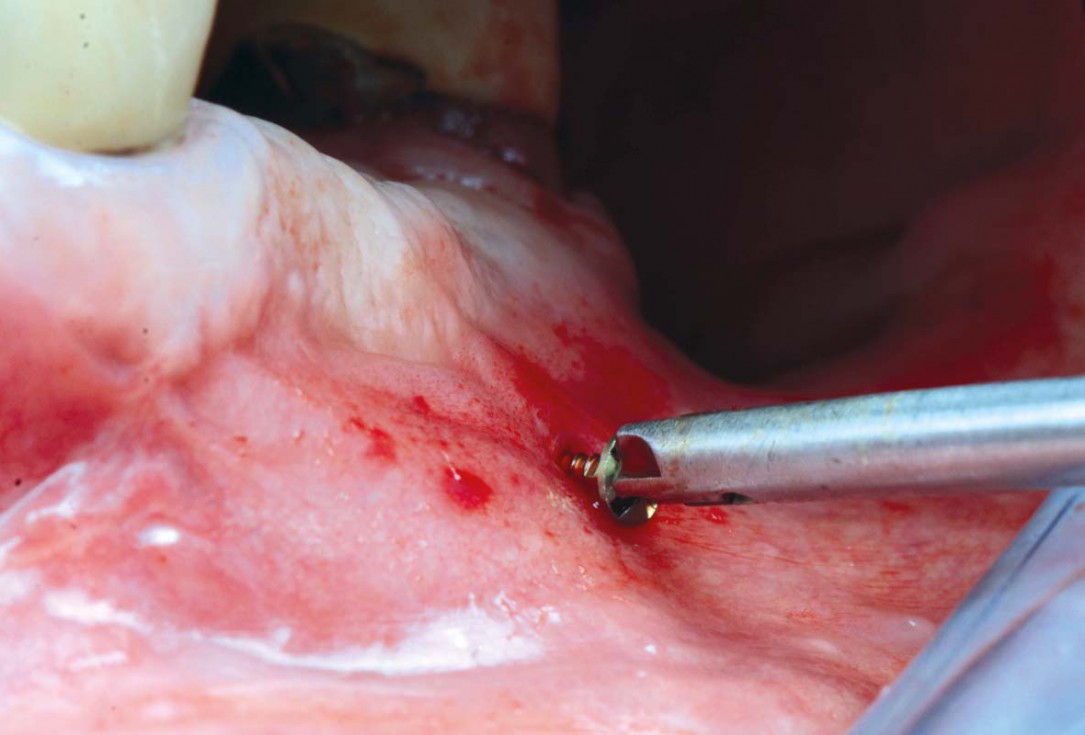

Preoperative situation – Maxillary defect in area 14-16 (loss of implant 16 due to periimplantitis, tooth 14 extracted recently and area 15 already edentulous for a while)